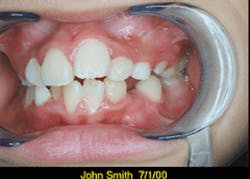

With Picture CD software included on the disk, you can add a patient`s name and the date taken to each image.

The software on the disk will enable you to view and modify the images, enhance color, rotate the images, and add a patient`s name and the date taken to each image. You can print the images in various sizes. You can even print several images to a single 81/2 x 11-inch sheet.